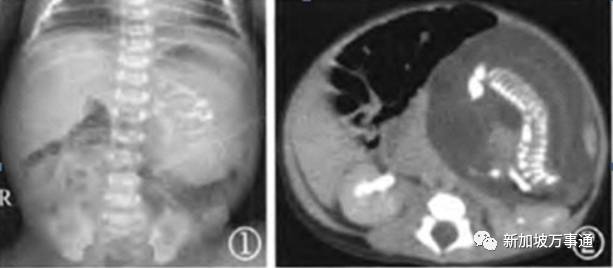

在他15岁的时候,少年的腹痛已经变得无法忍受,家人紧急将他转到大医院就诊,医生发现他腹部有柔软的肿块,扫描检查发现近23.8厘米长的异物,这一切都是肿瘤的征兆,大家自然而然都认为少年得了肿瘤。

然而,就在少年做了CT后,整个事件就变得扑朔迷离,就连医生也感到震惊不已!——这个肿块中竟然发现了脊柱!

肿瘤的诊断马上就被*翻推**了,再检查后他们陆续的发现了肿块中可见的变形头骨、脊椎,这绝不是肿瘤,而是一个畸形胎儿!!!

来源:BMJ 案例报告